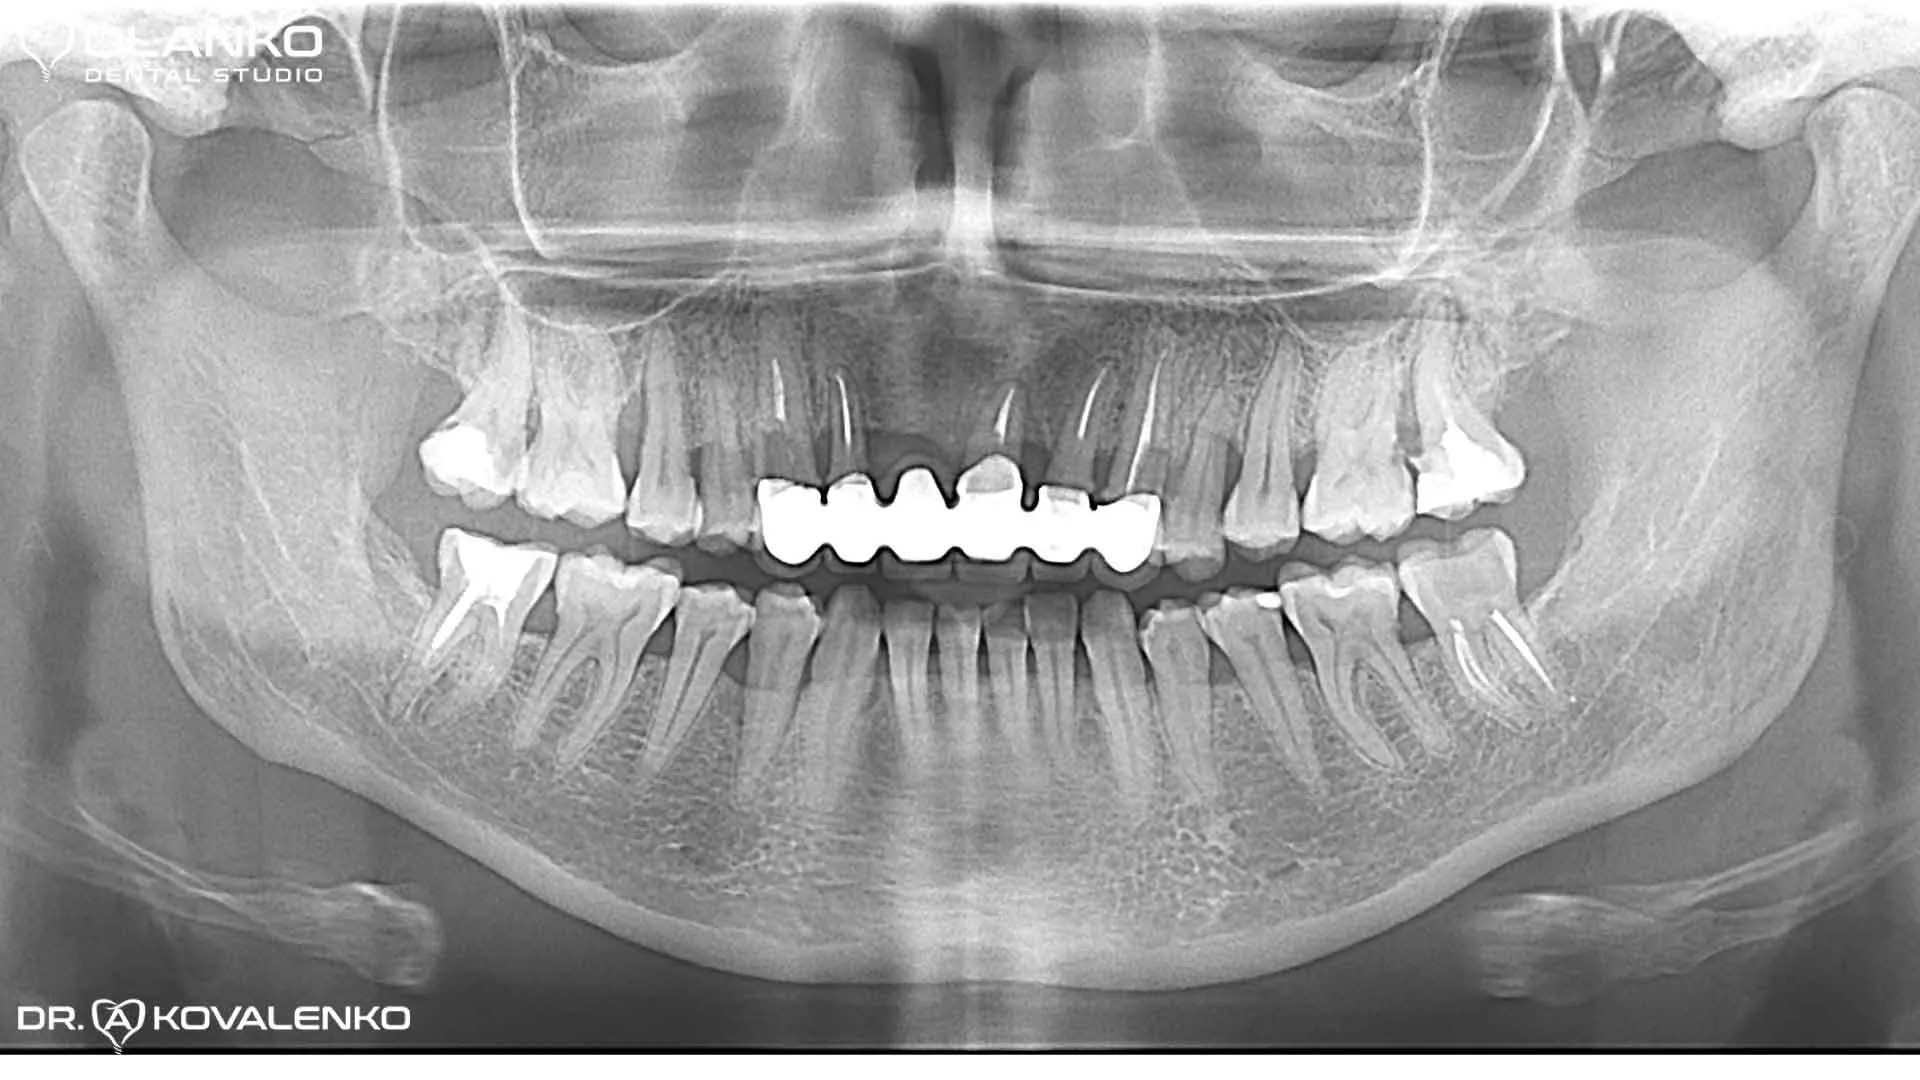

Контрольный панорамный рентген снимок после окончания протезирования на имплантатах

Проведено удаление 5 несостоятельных зубов с одномоментной имплантацией, костной и десневой пластикой. Установлено четыри зубных имплантата Straumann Roxolid SLA. Через 4 месяца проведено протезирование, на имплантаты установлен безметалловый мостовидный протез из диоксида циркония.